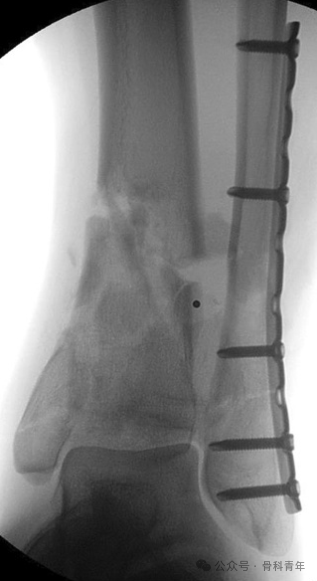

胫骨内侧钢板固定。

内侧支持钢板固定